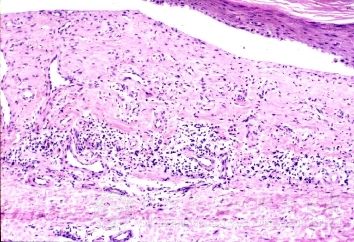

北京京城皮肤医院指出,肛门瘙痒的症状:为较常见的局限性瘙痒症,多见于中年男性,往往局限于肛门周围,有时向前蔓延至阴囊,向后至臀沟两侧,女性亦可发病,儿童患蛲虫病也可以引起肛门瘙痒症。